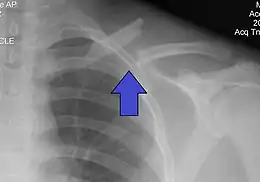

Il est radiographique affirmé par la radiographie de face. Idéalement il s'agit d'un cliché « clavicule de face » ascendant à 30° sur l'horizontale qui visualise mieux l'os et le foyer. Le fragment proximal est habituellement déplacé vers le haut en raison de la traction du muscle sterno-cléido-mastoïdien, le fragment distal étant attiré vers le bas par le poids de l'épaule et la traction du muscle deltoïde. Il se produit un raccourcissement par perte de l'arc boutant claviculaire avec un déplacement du moignon de l'épaule vers la ligne médiane.